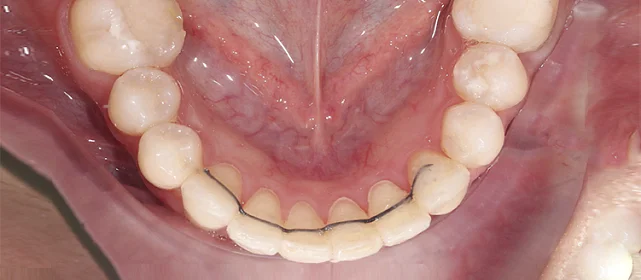

Зубы выровнены, смыкание нормализовано. Установлены несъёмные ретейнеры на обе челюсти, сняты сканы для ретенционных кап. Консультация ортопеда запланирована на более поздний срок.

Основной набор из 34 кап выполнил бо́льшую часть работы, но для финальной коррекции смыкания понадобился дополнительный комплект. Это не редкость — зубы двигаются с разной скоростью, и последние доли миллиметра часто требуют доработки. В итоге получили стабильный результат, который зафиксировали ретейнерами.